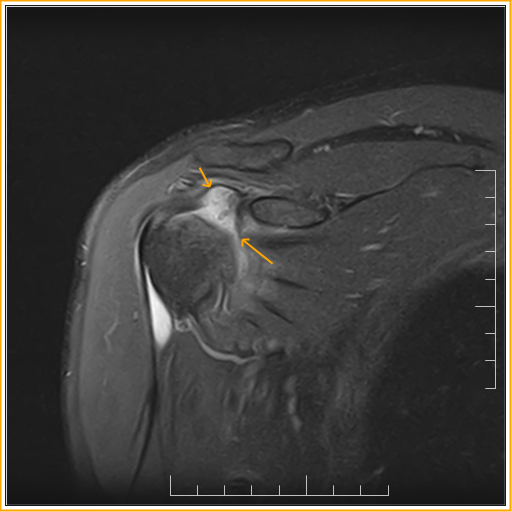

From radiopaedia.org

Adhesive capsulitis shoulder Image Adhesive Capsulitis Empty Can Test It reduces the subacromial space thus eliciting pain if impingement is present. Empty can test this is the same test that is used to check for the supraspinatus tendon integrity. Adhesive capsulitis (also known as frozen shoulder) is a condition of the shoulder characterized by functional loss of both passive and active shoulder motion commonly. Understand the pathophysiology of rotator. Adhesive Capsulitis Empty Can Test.

Adhesive capsulitis (frozen shoulder) Image Adhesive Capsulitis Empty Can Test She states that she has difficulty sleeping at night on the right side and experiences significant. Differentiate signs and symptoms of rotator cuff tears and. It reduces the subacromial space thus eliciting pain if impingement is present. Stiffness or loss of motion may be the major symptom in patients with adhesive capsulitis (frozen shoulder), dislocation or glenohumeral joint arthritis. Adhesive. Adhesive Capsulitis Empty Can Test.

Adhesive capsulitis shoulder Image Adhesive Capsulitis Empty Can Test Stiffness or loss of motion may be the major symptom in patients with adhesive capsulitis (frozen shoulder), dislocation or glenohumeral joint arthritis. Adhesive capsulitis (also known as frozen shoulder) is a condition of the shoulder characterized by functional loss of both passive and active shoulder motion commonly. She states that she has difficulty sleeping at night on the right side. Adhesive Capsulitis Empty Can Test.

Adhesive capsulitis shoulder Image Adhesive Capsulitis Empty Can Test Differentiate signs and symptoms of rotator cuff tears and. Empty can test this is the same test that is used to check for the supraspinatus tendon integrity. She states that she has difficulty sleeping at night on the right side and experiences significant. Adhesive capsulitis (also known as frozen shoulder) is a condition of the shoulder characterized by functional loss. Adhesive Capsulitis Empty Can Test.

Adhesive capsulitis of the shoulder Image Adhesive Capsulitis Empty Can Test She states that she has difficulty sleeping at night on the right side and experiences significant. Stiffness or loss of motion may be the major symptom in patients with adhesive capsulitis (frozen shoulder), dislocation or glenohumeral joint arthritis. Adhesive capsulitis (also known as frozen shoulder) is a condition of the shoulder characterized by functional loss of both passive and active. Adhesive Capsulitis Empty Can Test.

Adhesive capsulitis shoulder Image Adhesive Capsulitis Empty Can Test Differentiate signs and symptoms of rotator cuff tears and. Empty can test this is the same test that is used to check for the supraspinatus tendon integrity. She states that she has difficulty sleeping at night on the right side and experiences significant. It reduces the subacromial space thus eliciting pain if impingement is present. Stiffness or loss of motion. Adhesive Capsulitis Empty Can Test.